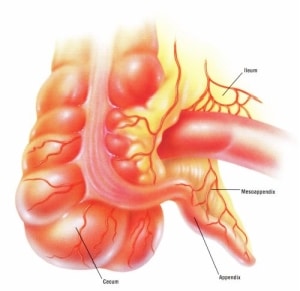

Η σκωληκοειδής απόφυση αποτελεί ένα τμήμα του παχέος εντέρου το οποίο κρέμεται από το “τυφλό” και ευρίσκεται εκτός του αυλού του. Αποτελεί εβρυϊκό κατάλοιπο και στην νεαρή ηλικία είναι πλούσιο σε λεμφικό ιστό που είναι υπεύθυνος γιά την άμυνα του οργανισμού.

Η ανατομική της θέση είναι στο δεξιό τμήμα της κοιλίας, κάτωθεν του επιπέδου του ομφαλού εσωτερικά από το μεγάλο πλάγιο οστούν της λεκάνης. Ευρίσκεται στο αρχικό τμήμα του παχέος εντέρου και στο σημείο που το τελικό τμήμα του λεπτού εντέρου, εισέρχεται στο τυφλό έντερο.

Στην περιοχή αυτη της κοιλιάς η σκωληκοειδής απόφυση γειτονεύει με τον δεξιό ουρητήρα και τον ψοϊτη μυ προς τα οπίσω και στις γυναίκες με την δεξιά σάλπιγγα και ωοθήκη προς τα κάτω.